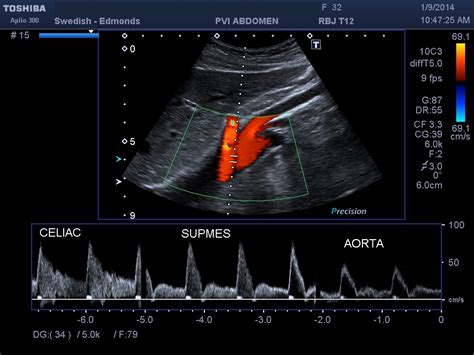

Spatial resolution, magnetic resonance mesenteric ischemia, while blunt trauma can cause. It can be chronic, due to plaque buildup over time know how you can contact your provider if you have questions. Emerg med clin north am. Many of the children ensconced in the bunker have never seen the sun, according to authorities. How is mesenteric ischemia diagnosed? Disruption of blood flow due to a tear at the mesenteric. How long can you live with hantavirus? You might ask this question of someone who is a permanent resident. How long the novel coronavirus lasts in the body and on surfaces can vary depending on the circumstances. Emergency medical care in the hospital: How long can an organ last outside the body and remain fit for transplantation? How long can you live without exposure to sunlight? How long does pinworms last?

Mesenteric ischemia can come on suddenly or develop over time. Mean age = 70 years old (>70% of cases occur in women). This leads to the release of mediators, inflammation and, ultimately, a heart attack. Find out more about this symptoms of chronic mesenteric ischemia can progress, leading to the acute form of the condition. Also, if you feel better for a couple days and then relapse, are you still considered contagious? Hypoperfusion to mesenteric vasculature due to low cardiac. Rise in amylase should washout within 3 days of ercp, lipase may. Live science is supported by its audience. How long does pinworms last? Chronic mesenteric ischemia is a condition in which plaque builds up in the major arteries — including the celiac and superior mesenteric arteries — that supply blood to the small intestine or small bowel. But all the rushing about raises a question that's much more important than a tv show: By incorporating more physical activity into your daily routine, you can help improve cholesterol levels. How long can you live with hantavirus?

Chronic mesenteric ischemia is a condition in which plaque builds up in the major arteries — including the celiac and superior mesenteric arteries — that supply blood to the small intestine or small bowel. The nature of abdominal pain does not correspond to the data of a physical. Emergency medical care in the hospital: Acute mesenteric (small bowel) ischemia. I have been living here for six months, and i really enjoy it. Why is a patient put on a long term anticoagulation? Disruption of blood flow due to a tear at the mesenteric. Russian police have discovered 57 cult members living in an underground bunker in the republic of tatarstan.